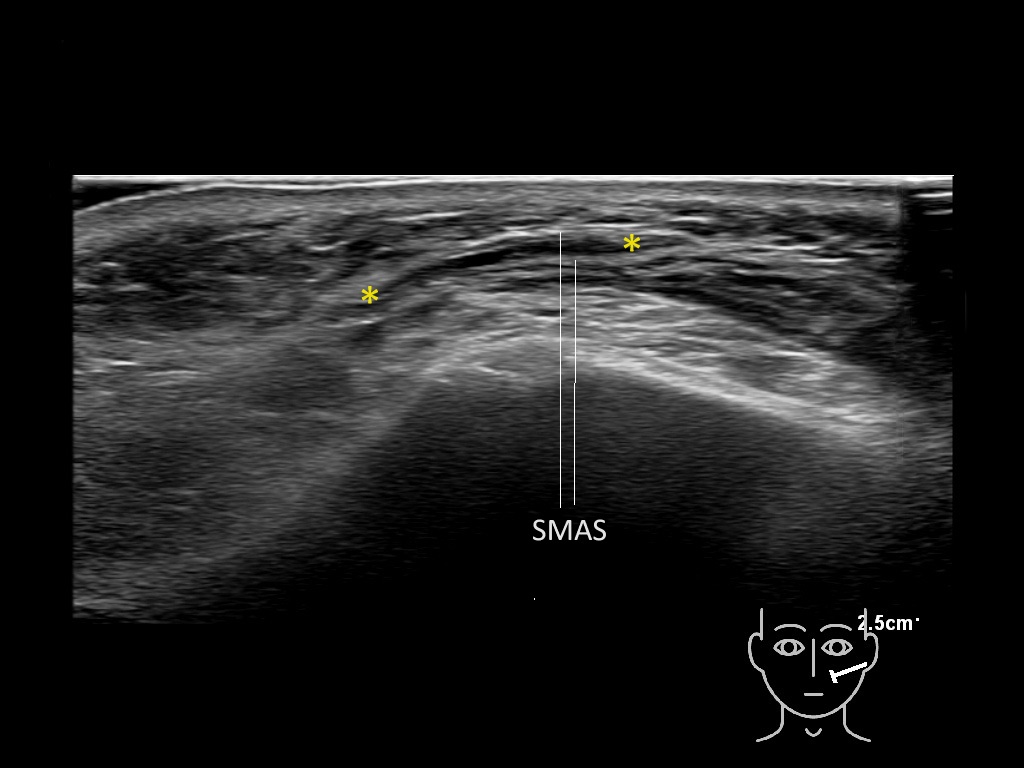

Filler deposits may end up unintentionally in the SMAS or fascial layers of the skin. Very often this will not lead to adverse events, however, adverse events ( nodules, migration / redistribution impaired muscle movement and smiling and malar edema) are are often related to filler ending up in the SMAS or fascia.

Study the first image to recognize the different layers. If you are sure about the layers, swipe to the second image to view the answer (if applicable).